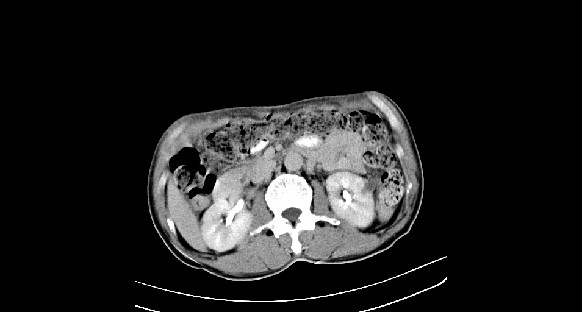

男性,70岁,体检b超发现左肾占位,请各位战友发表一下观点

左肾有两个病灶,且较大的病灶内可见点状钙化灶,增强扫描边缘也是呈渐进性强化,中央部分未见明显强化